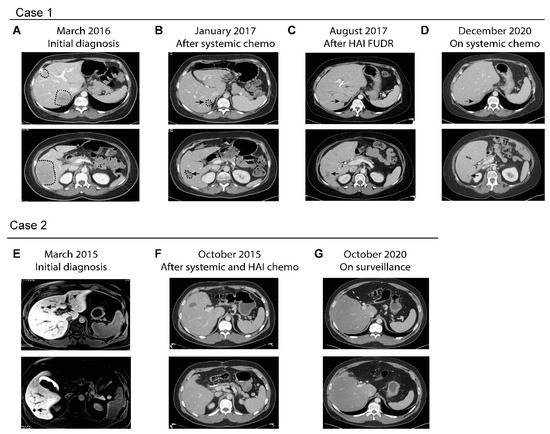

A 45-year-old otherwise healthy woman presented with intermittent left lower quadrant pain and decreased stool caliber over one year. A computerized tomography (CT) scan done in March 2016 showed multiple liver lesions in bilateral liver lobes, focal segmental thickening of the sigmoid colon with adjacent sigmoid mesocolon lymph nodes (Figure 1A). She subsequently underwent an ultrasound-guided liver biopsy of one of the liver lesions, which showed adenocarcinoma consistent with colorectal primary. Colonoscopy revealed a near-obstructing sigmoid colon mass, which was biopsied showing adenocarcinoma. Initial serum CEA level was 874 ng/mL. Molecular profiling of the tumor samples showed proficient MMR and no RAS/BRAF mutations. She was treated initially with FOLFIRI and panitumumab every two weeks, which led to rapid resolution of all her symptoms. She continued to stay on chemotherapy, which was later de-escalated to maintenance 5-FU and panitumumab. After ten months of chemotherapy, her CT scans showed marked treatment response in the liver and sigmoid colon (Figure 1B). Per tumor board recommendations she underwent sigmoid colectomy, wedge resections of liver lesions and placement of HAIP in March of 2017. Surgical pathology showed residual adenocarcinoma in the resected sigmoid colon and liver lesions. None of the twenty-three peri-colonic lymph nodes showed evidence of malignancy. She was subsequently treated with six cycles of FUDR delivered monthly via HAIP (14 days of FUDR alternating with 14 days of heparin/saline/dexamethasone), concurrently with biweekly systemic 5-FU and panitumumab. Subsequent CT scans showed no evidence of disease other than postsurgical changes in the liver. Serum CEA levels also fell to normal range. Due to malfunction, her HAIP was subsequently removed. She underwent surveillance until August 2018, when CT scans showed disease recurrence presenting as a large pelvic mass and multiple lung lesions. However, no evidence of disease was detected in the liver (Figure 1C). She subsequently underwent resection of the pelvic mass and was restarted on systemic chemotherapy, FOLFIRI plus panitumumab. Her most recent CT scans in December 2020, close to five years after initial diagnosis and two years after extrahepatic recurrence, showed stable disease in her lungs, which are the only organ affected, and no evidence of liver metastasis (Figure 1D). She continues to stay on maintenance 5-FU and panitumumab.

Figure 1.

Serial imaging studies of two representative cases treated with systemic and HAIP chemotherapy. (A–D) Serial CT images of Case 1. The patient initially presented with metastatic sigmoid colon cancer with bulky disease burden in the liver (A). After prolonged treatment with systemic FOLFIRI and panitumumab which led to good treatment response (B), she subsequently underwent surgical resection of the primary colon cancer and liver lesions and placement of HAIP. (C) CT scans after completion of systemic and HAIP chemotherapy showed post-surgical changes (arrows) which remain unchanged over the following three years (D) despite extrahepatic recurrence. (E–G) Serial imaging of Case 2. (E) Initial MRI showing multiple lesions in Case 2 who had just undergone sigmoid colectomy. The patient was treated with 4 cycles of chemotherapy followed by left liver resection, ablation of liver lesions and placement of HAIP. (F) CT after completion of adjuvant systemic and HAIP chemotherapy showed post-surgical changes which remain stable over the following five years (G).

This is an example demonstrating the ability of HAIP chemotherapy in successfully controlling liver metastases after a prolonged course of systemic chemotherapy. As reported [49], the patient eventually did develop pelvic recurrence, which was surgically removed, and lung metastases, which are now treated with systemic chemotherapy. It is plausible to speculate that her disease course could have been more challenging and her survival shorter if she had liver metastases during the course of treatment, which may have limited her treatment options if her liver function was compromised.

5.2. Case 2

A 31-year-old man with no family history of colorectal or gastrointestinal cancers presented with hematochezia. A colonoscopy revealed a bleeding mass in the proximal sigmoid colon, which was biopsied showing invasive moderately differentiated adenocarcinoma. CT scans showed a sigmoid mass with regional lymphadenopathy and no evidence of distant metastasis. In February 2015, he underwent a low anterior resection with regional lymphadenectomy. Surgical pathology revealed moderately differentiated adenocarcinoma measuring 2.6 cm with 14 of resected 29 lymph nodes being involved. Molecular profiling showed the tumor had proficient MMR and KRASG12D mutation. Unfortunately, postsurgical CT scans showed at least four suspicious new liver lesions, which were better delineated by MRI (Figure 1E). One liver lesion was later biopsied and confirmed to be metastatic moderately differentiated adenocarcinoma. Per tumor board recommendation, he underwent four cycles of FOLFOXIRI plus bevacizumab followed by exploratory laparotomy, which included left lateral segmentectomy of the liver, microwave ablation of the remaining right liver lesions and placement of an HAIP. Microwave ablation of the right liver lesions were performed, instead of hepatic resection, as a parenchyma-sparing strategy. Surgical pathology revealed metastatic adenocarcinomas in the left liver with marked treatment necrosis. After surgery, he completed 4 months of adjuvant 5-FU (oxaliplatin omitted due to allergic reaction) concurrently with 6 cycles of HAIP FUDR. Post-treatment CT scans showed no evidence of metastatic disease other than post-ablative changes in the liver (Figure 1F). He remained in remission for the following five years (Figure 1G) and is currently being followed semiannually.

This case demonstrates the potential benefit of HAIP, in conjunction with perioperative systemic chemotherapy, in a patient with multiple liver metastases. It is worth noting that his liver metastases were detected immediately after the primary colon surgery, which also yielded extensive locoregional lymph node involvement. Given the extensiveness of his disease, young age and the goal for long-tern remission, he was treated with FOLFOXIRI plus bevacizumab in order to attain the deepest possible treatment response prior to liver resection. Subsequent adjuvant HAIP and standard systemic chemotherapy was able to put him in remission for more than five years.